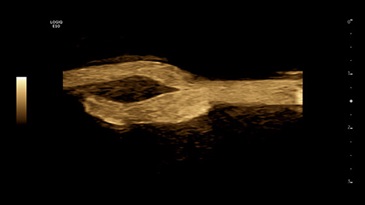

Бифуркация сонной артерии с помощью B-Flow, L2-9-D